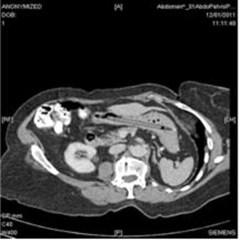

“Una donna di 76 anni è giunta all’osservazione urgente dei medici per perdita di peso e diarrea. Un’indagine sigmoidoscopica ha mostrato una grave diverticolite e una successiva TAC addominale ha messo in evidenza la presenza di un oggetto estraneo di forma allungata nello stomaco, ma nessun’altra anomalia. I sintomi si sono poi risolti spontaneamente. Nel corso della visita la donna si è ricordata di aver ingoiato per sbaglio una penna 25 anni prima. La stava usando per toccare delle placche su una tonsilla quando le è sfuggita e non ha potuto evitare di inghiottirla. E in effetti una gastroscopia ha dimostrato la presenza di una penna con la punta di feltro nello stomaco (cliccare per ingrandire), ma senza evidenze di lesioni gastriche. Il caso è stato poi discusso in un consesso di gastroenterologi che ne hanno consigliato la rimozione nonostante non avesse provocato danni per ben 25 anni al fine di evitare eventuali perforazioni del duodeno. La penna dunque è stata rimossa mediante intervento endoscopico”.